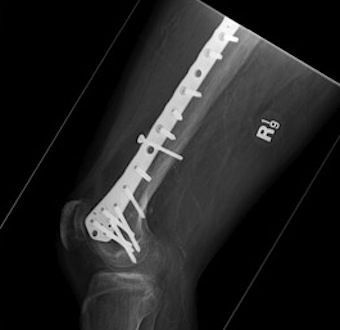

Plate + Nail

Distal Femoral Replacement

Indications

Elderly osteoporotic patient

Unreconstructable distal femur

Multiple co-morbidities

Difficulty non weight bearing